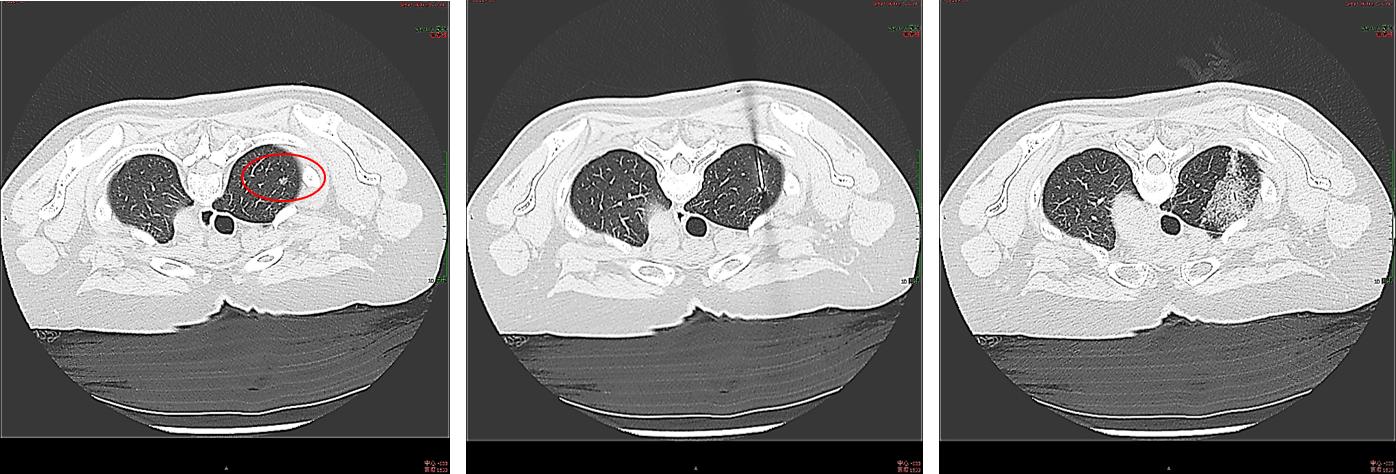

女性患者,56岁,肺部原位腺癌切除史,随访过程中发现GGO在增大

术前活检出血量多

低功率微波消融后出血量明显减少